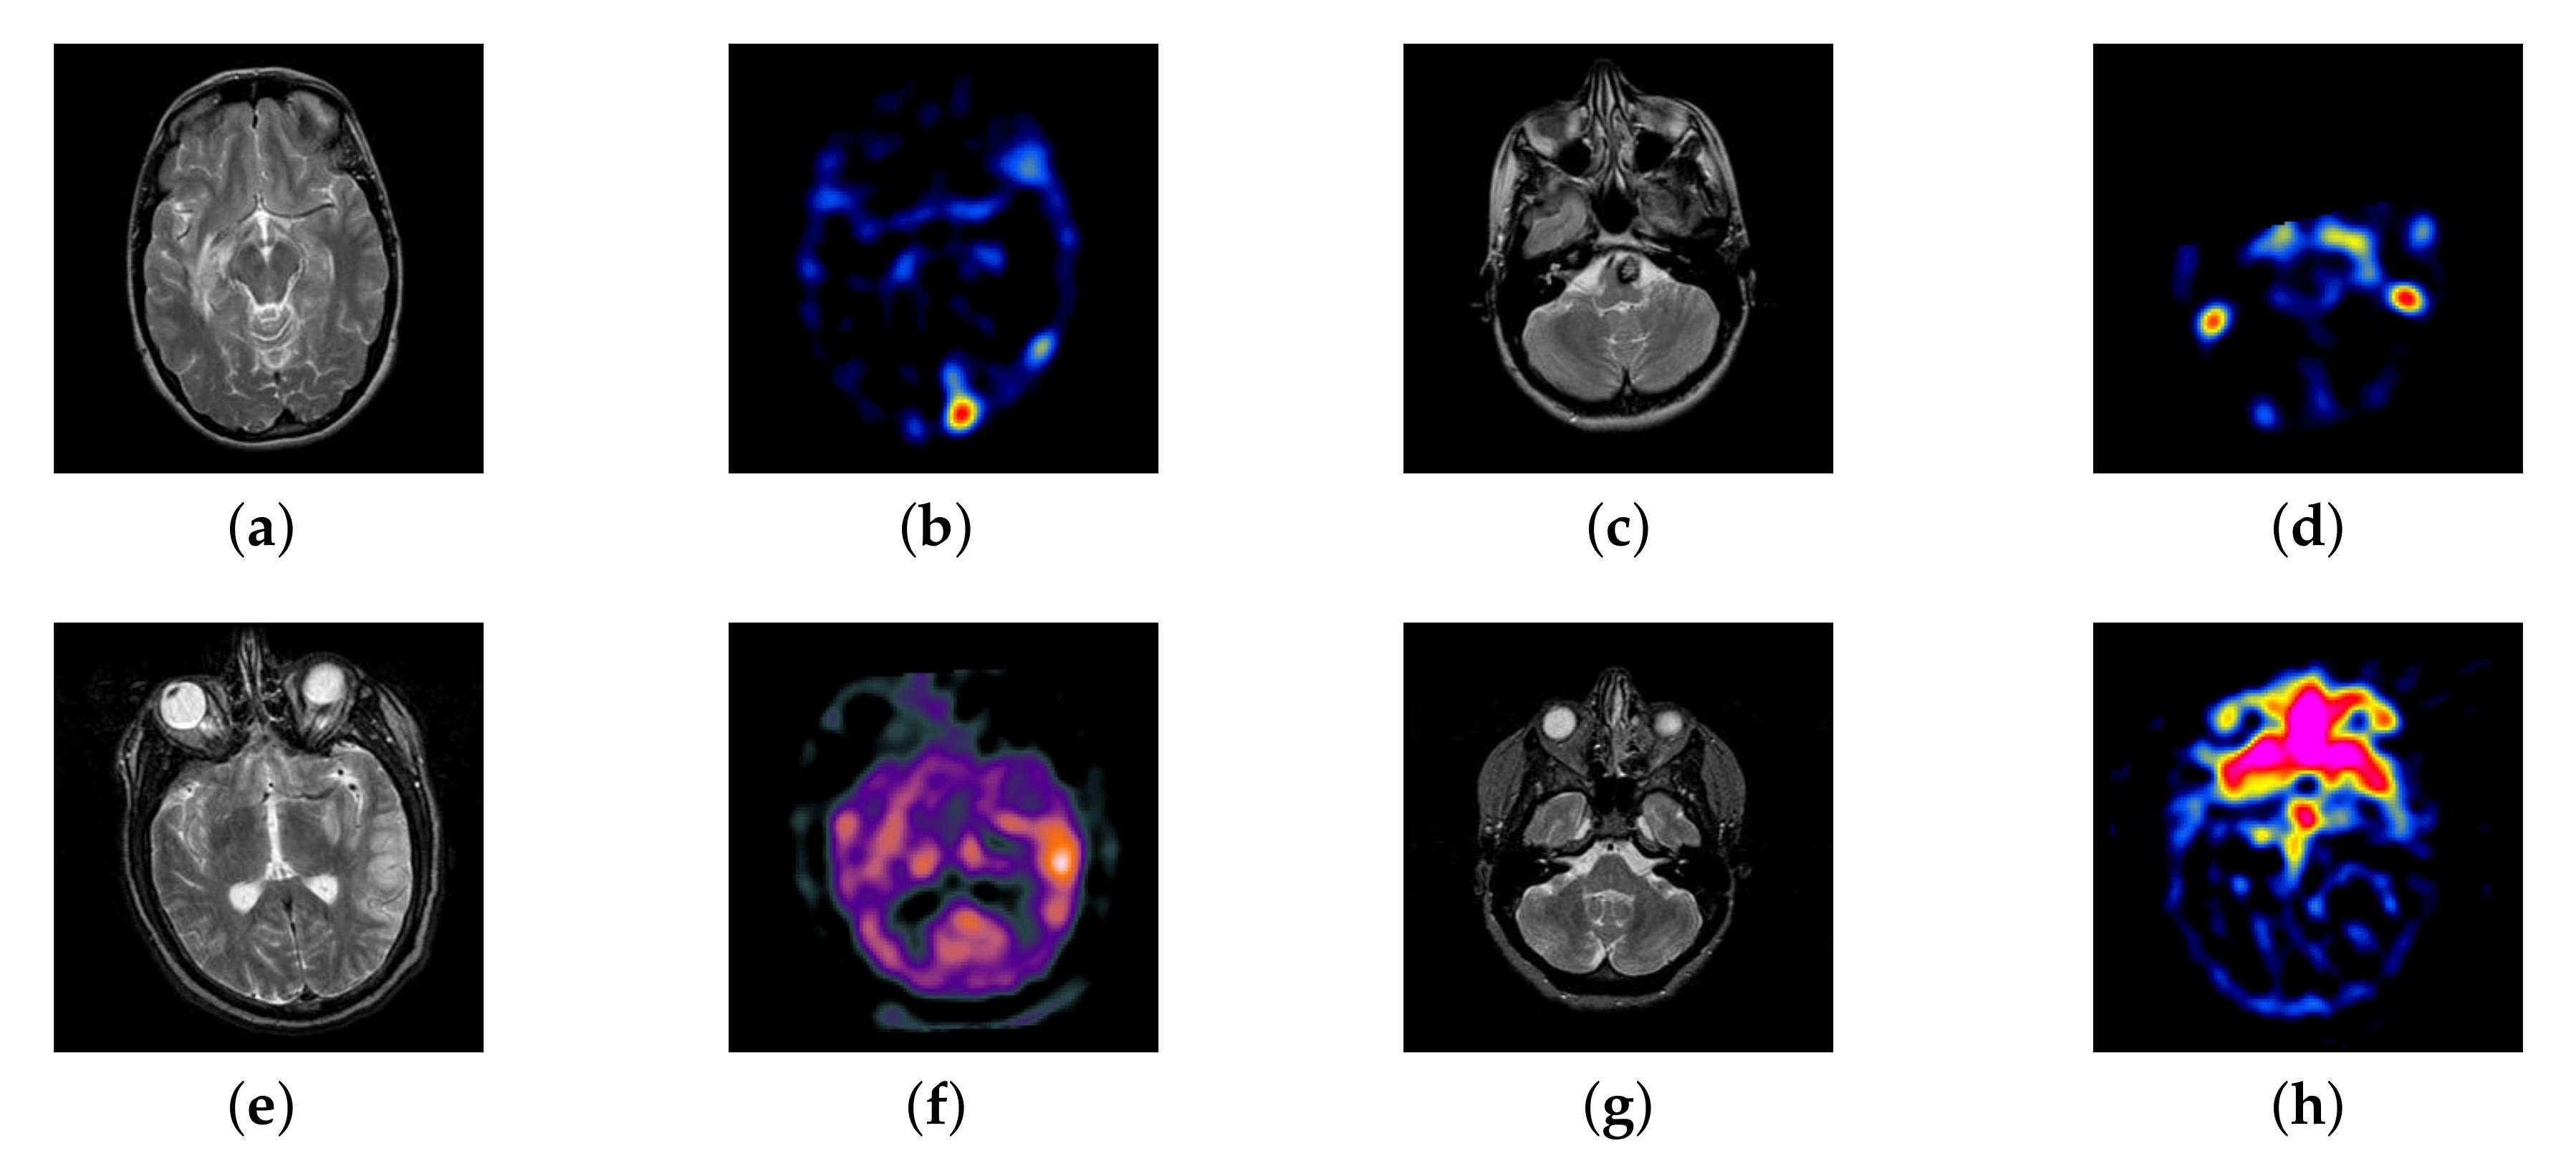

4.2. The Fusion of MRI-SPECT

SPECT image can absorb radionuclide distribution diagram from different directions in vivo and draw the distribution. Three-dimensional reconstruction diagram of radionuclides in each cross section in vivo after computer comprehensive processing. It is something that structural MRI does not have. So, the combination of the two could allow doctors to get more accurate physiological information.

In this section, there are four multi-modal image sets and each set is consist of MRI image and SPECT image that are corresponding to the sanme location slice of the brain as shown in Figure 7. Among them, Figure 7e,f are captured from patients who have suffered a subacute stroke. Figure 7a–d,g,h are captured from patients who have brain tumor. The fused images with different fusion methods based on DTCWT, NSCT, GFF, LPSR, IGM, DDcGAN, FusionCNN, and the proposed methods are shown in Figure 8, Figure 9, Figure 10 and Figure 11. It can be seen that the fused images obtained by LPSR and FusionCNN algorithm have serious color distortion. Based on DTCWT and NSCT algorithm, the fusion image structure information is not obvious. The fused images obtained by GFF and IGM algorithm contain almost no color information, which is not conducive for doctors to make correct diagnosis. The image obtained by the DDcGAN algorithm saves the color information in the SPECT to a great extent; however, the brightness of the fused image is too large, which causes the image to have no sense of hierarchy and the contrast to decrease. By comparing with other algorithms, we find that our algorithm has good color retention effect, clear structure information, moderate brightness, and no artifacts.

Figure 7.

Four pairs of magnetic resonance imaging (MRI)-single-photon emission computed tomography (SPECT) source images: (a,c,e,g) are MRI images; (b,d,f,h) are SPECT images.